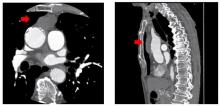

The authors have previously reported on a subxiphoid single-port thymectomy [3]. As a camera is inserted into the midline of the body, the subxiphoid approach facilitates identification of the bilateral phrenic nerves and also provides a good visual field in the neck region compared with that afforded by the lateral thoracic approach. However, the limited operability afforded by the subxiphoid approach renders it unsuitable for procedures which require suturing. The authors have previously reported on subxiphoid dual-port thymectomy, involving placement of an additional port in the intercostal space in the right anterior chest, along with the subxiphoid port. Use of dual ports creates a better visual field, reduces instrument interference, and offers excellent operability for advanced surgeries. This is the case of a patient with an anterior mediastinal tumor. A subxiphoid dual-port thymectomy was performed with partial resection of the innominate vein and pericardial patch closure.